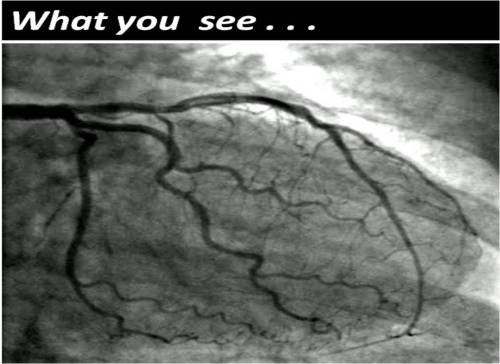

Human coronary circulation stands unique among others as it is a life-sustaining circulation.It is considered a great medical achievement to visualise the right and left coronary artery system by coronary angiogram. Actually what we see is only a fraction of the surface area of coronary circulation . The surface area of epicardial coronary arteries constitutes less than 5 % of entire coronary vascular tree .

This is the reason normal coronary angiogram can never mean normal coronary circulation !

An in vitro heart with special catheters showing the true extent of coronary circulation: Courtesy http://eurheartj.oxfordjournals.org/content/28/3/278.full.pdf+html